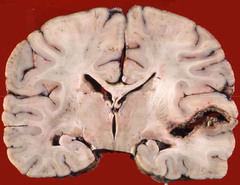

vascular dementia gross findings

Front

cerebral atrophy and ex vacuo hydrocephalus from reduction in white matter multifocal lacunar infarcts

Back